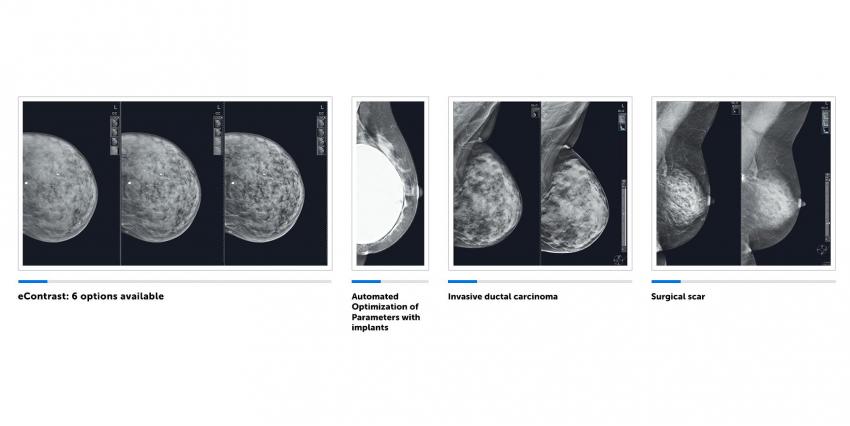

The Senographe Pristina system is a three-dimensional (3D) digital breast tomosynthesis (DBT) platform that provides excellent breast imaging without increased radiation exposure. Tomosynthesis (volumetric, three-dimensional mammary gland image) is based on ASIRDBT, a calcification artifact correction iterative reconstruction algorithm. It provides off-plane images that exceed the traditional Filtered Back Projection (FBP) algorithm. In addition, a specific cutting algorithm reflects calcification as if each lesion is located in its optimal plane, allowing doctors to easily read images.

The device is ready to use within a few minutes after the system starts up and does not require any complicated calibration. Switching the device between 2D mammography and DBT (digital breast tomosynthesis) modes is very convenient and can be done with a single click of the mouse. The possibility to select one of the six contrast levels in the 2D examination mode is equally important for quality diagnostics.